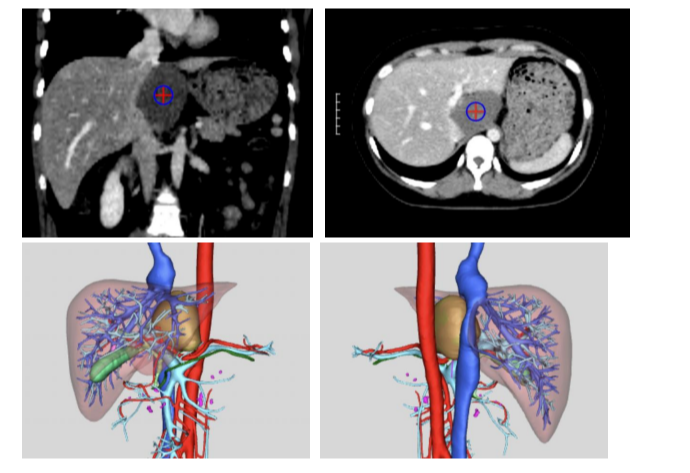

接診后,梁英健教授對金女士的病情進行全面深入評估。利用先進的三維可視化技術清晰地顯示血管瘤幾乎占據整個尾狀葉,且緊貼并部分包裹肝后最重要的下腔靜脈,同時還緊鄰著第一肝門及左肝靜脈。這意味著手術中稍有不慎,就可能損傷這些關鍵血管,引發致命性大出血。此外,三個月前的膽囊手術造成的腹腔粘連,也進一步增加了本次手術的難度。傳統開腹手術需要長達30厘米以上的切口,創傷大、恢復慢。經過細致的術前討論,憑借豐富的復雜腫瘤治療經驗,團隊精心制定了腹腔鏡微創手術方案,力求在完整切除腫瘤的同時,最大程度減少患者創傷。